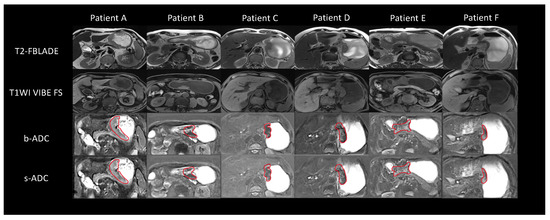

3.2. Image Quality Assessments Results and Analyses

3.4. ADC Measurement Assessment Results and Analyses